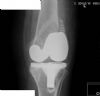

AP of Knee after fixation of peri-prosthetic fracture with 13 hole PERILOC plate and locking screws

History : 70 yr female, underwent PFC total knee replacement, then subsequent non-traumatic fracture 11 days post op

AP of Knee after fixation of peri-prosthetic fracture with 13 hole PERILOC plate and locking screws History : 70 yr female, underwent PFC total knee replacement, then subsequent non-traumatic fracture 11 days post op